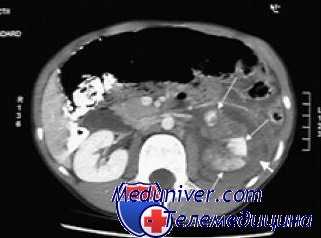

МРТ ОБП. Повреждение левой почки. Забрюшинная гематома (красная стрелка), отек перинефральной клетчатки (синяя стрелка).